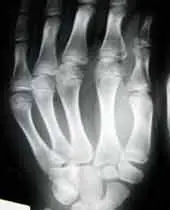

¿Por qué los rayos X sólo muestren los huesos?

Los rayos X se utilizan, en el campo de la medicina, para ver nuestro esqueleto. No solo nos muestran los huesos, también nos muestran los tejidos blandos, lo que ocurre, es que no quedan bien visibles y se ven como una mancha grisácea. Los rayos X son unos rayos radiactivos muy potentes, al hacernos una radiografía estos rayos atraviesan nuestro cuerpo, cuando llegan al hueso chocan, ya que el hueso es un tejido muy duro y no lo pueden atravesar como ocurre con los tejidos blandos. Cuando los rayos chocan con los huesos rebotan y nos devuelven, filtrados a través de un ordenador, la imagen de los huesos.Los tejidos blandos no se ven casi porque los rayos X los atraviesan. Los ultrasonidos o la resonancia magnética, son ideales para ver nuestros tejidos blandos.